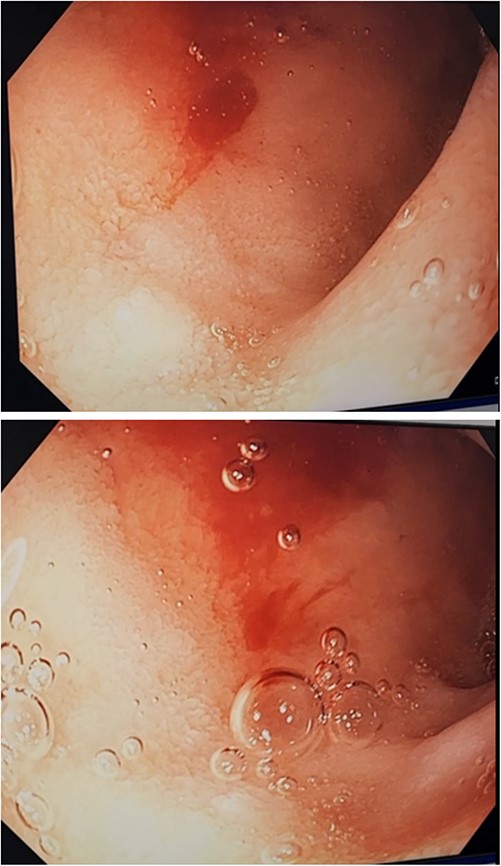

Three days after initial gastroscopy she developed further melena and anaemia, requiring additional PRBCs. She underwent a second gastroscopy, which demonstrated a lesion consistent with a DL at the junction of D1/D2 which was actively bleeding from an exposed vessel (Fig. 3). Haemostasis was achieved with thermocoagulation and adrenaline injection (Fig. 4). The melena resolved and haemoglobin remained stable. The remainder of her admission and 2-month follow-up were unremarkable.

Second gastroscopy – successful haemostasis of actively bleeding duodenal DL with thermocoagulation and adrenaline injection.